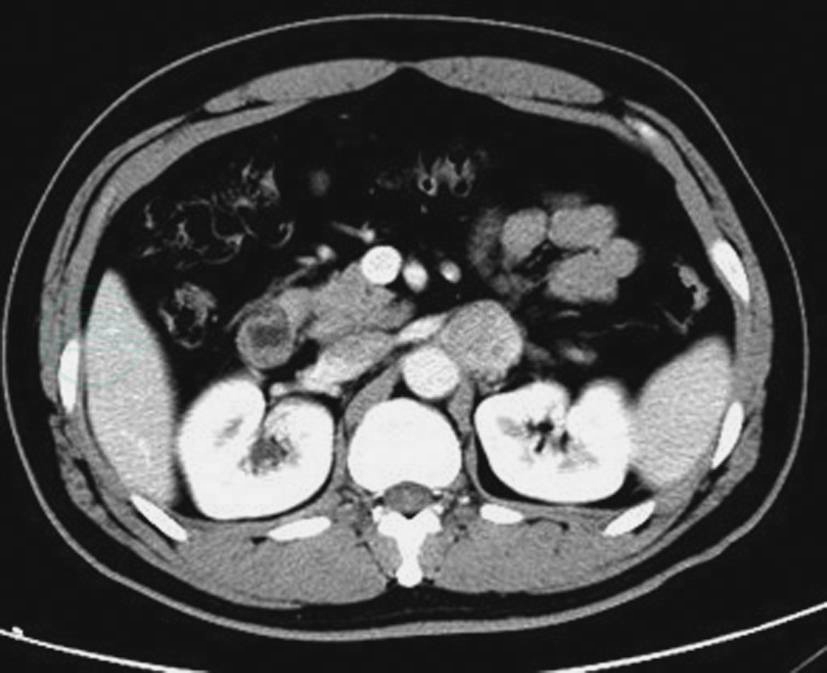

图3两侧肾上腺嗜铬细胞瘤

A.CT平扫示两侧肾上腺类圆形瘤体,密度尚均匀;B.CT平扫示两侧肾上腺瘤体,右侧瘤体不规则分叶状,左侧瘤体呈类圆形,其内囊变较明显